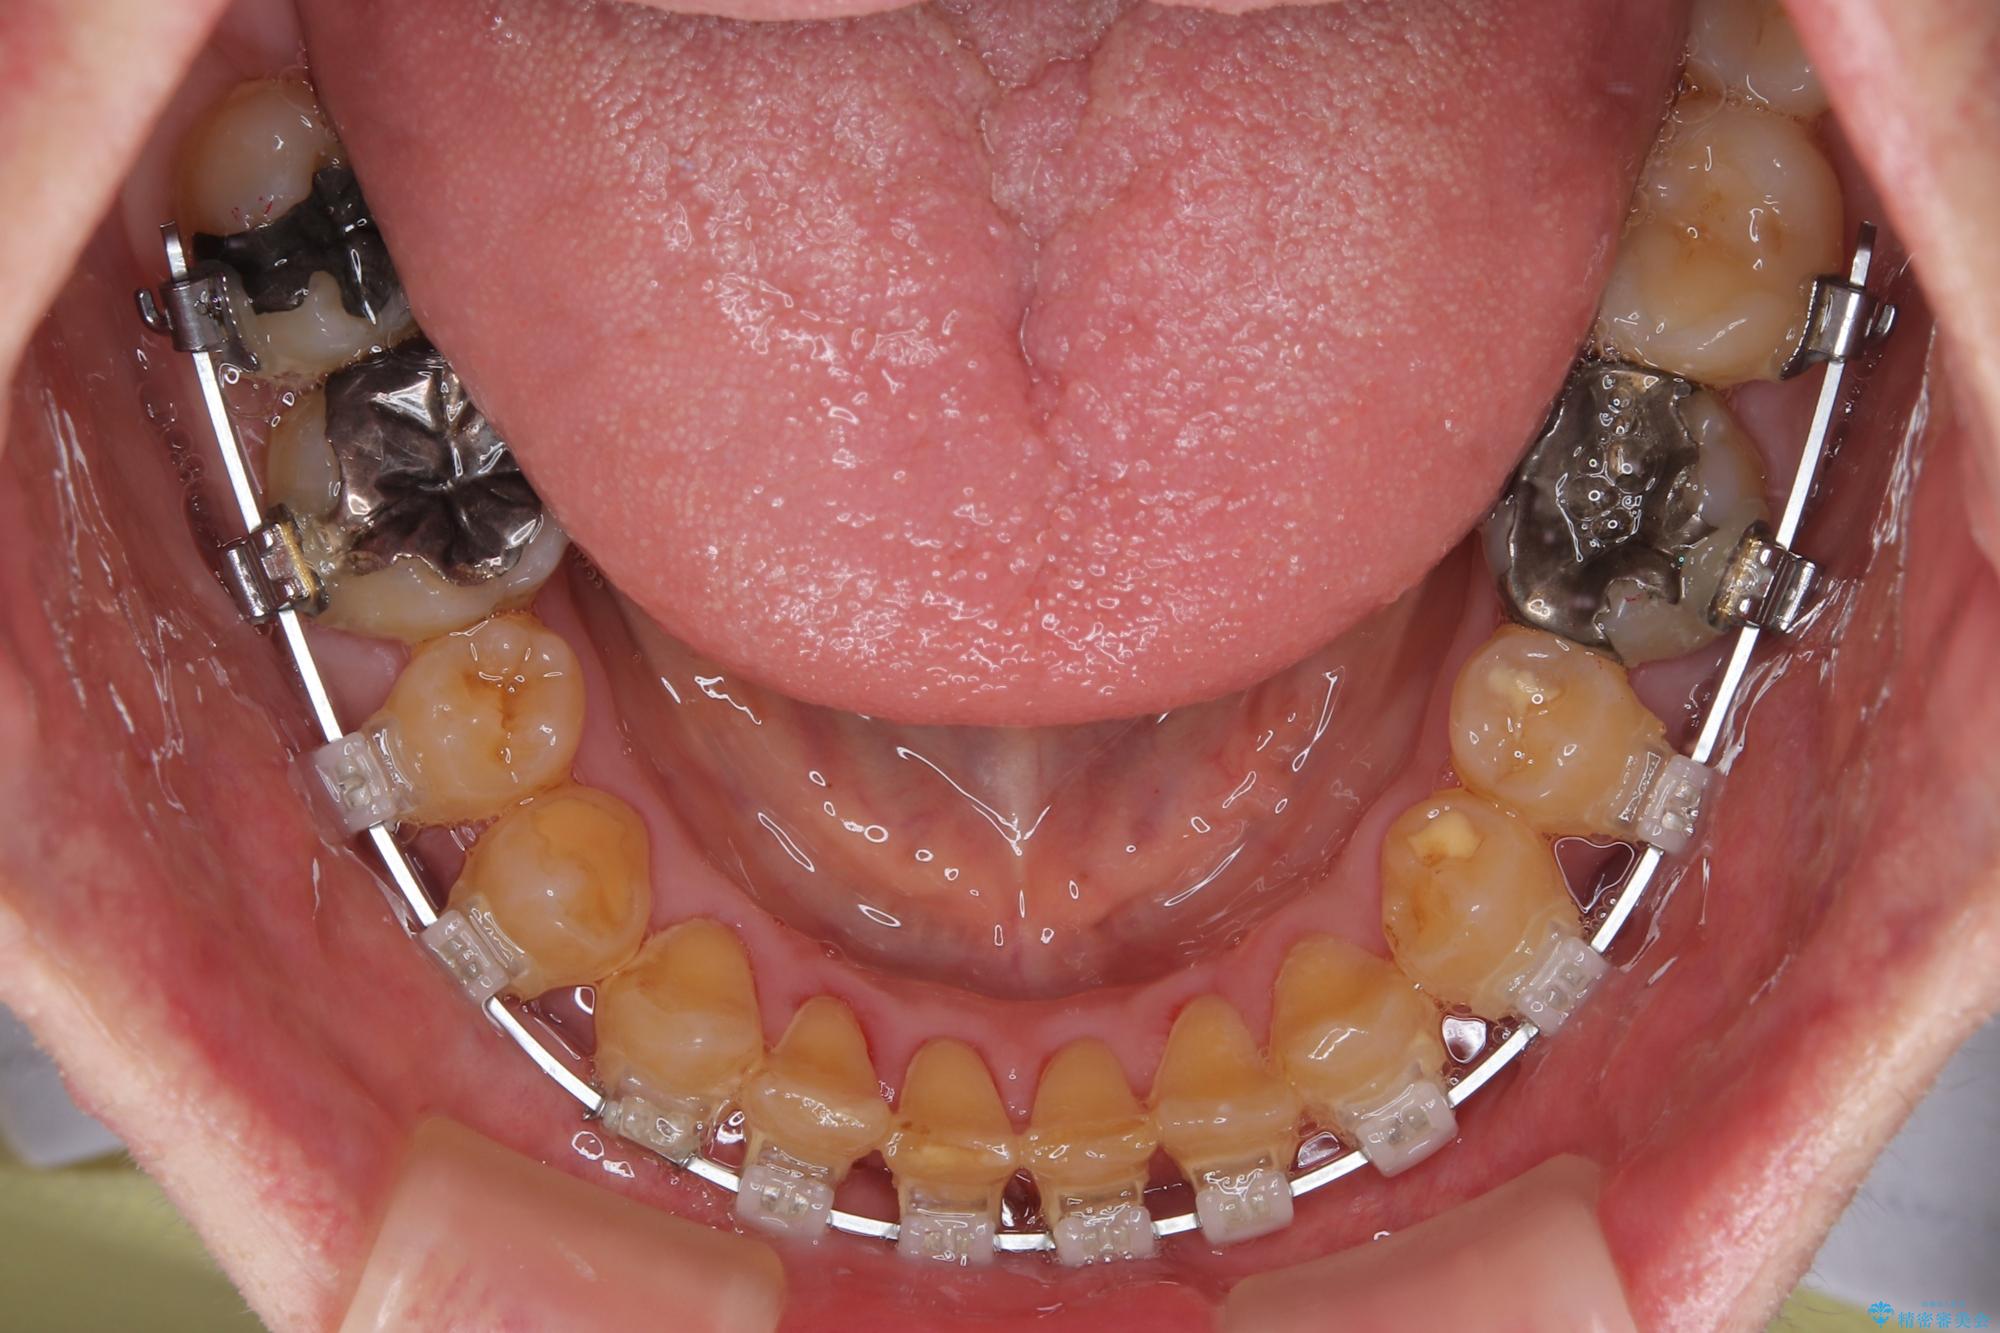

下顎前歯が隠れるほどのディープバイトにより、強い咬合力と突き上げで上顎歯列に隙間が空いている状態でした。

手前に傾斜している奥歯をワイヤー装置で立ち上がらせ、咬み合わせの高さを挙上することで突き上げを解消し、空隙歯列を改善していくこととしました。